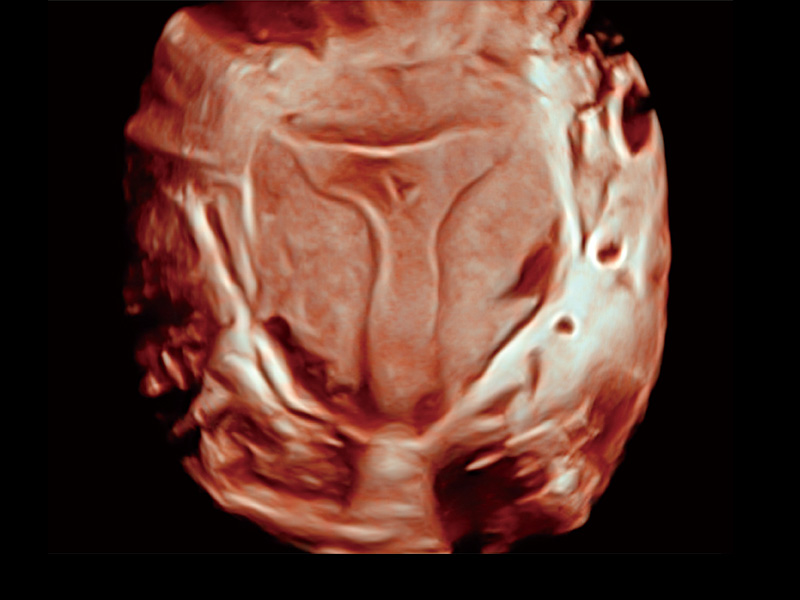

中央型宫腔粘连

单角子宫